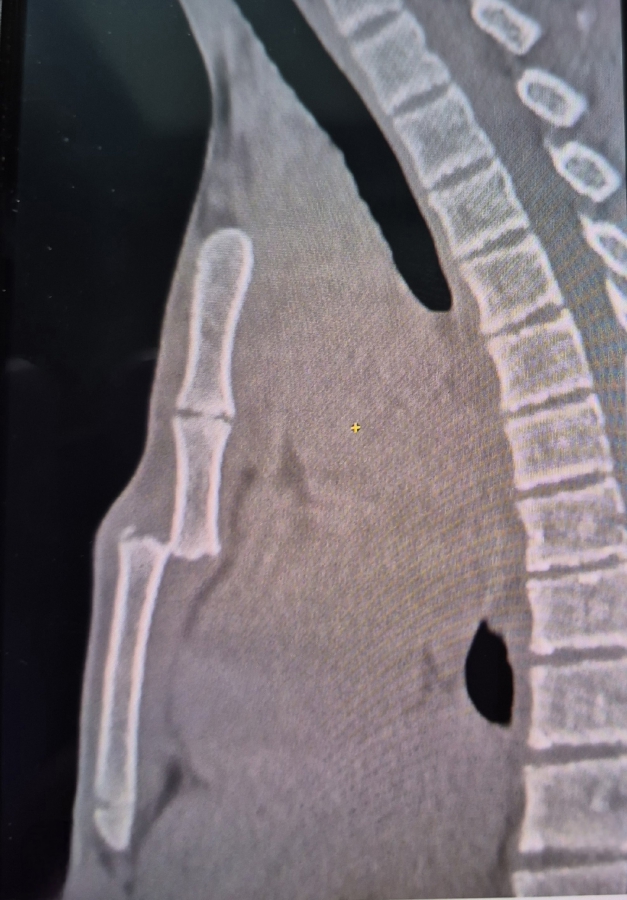

«У ребенка имеется перелом грудины со смещением, с полным смещением по ширине. Довольно редкая ситуация», — прокомментировал заведующий детского хирургического отделения БГКБ Валерий Захаров.

«Грудина становится сплошной в возрасте от 12 до 25 лет. До этого момента она растет, у нее есть зоны роста, за счет которых она увеличивается. У кого-то этот процесс завершается к 12 годам, у кого-то позже. По всей видимости, наш пациент сломал грудину по зоне роста. Если бы она у него была уже сплошной, он бы ее не сломал», — добавил заведующий отделением.